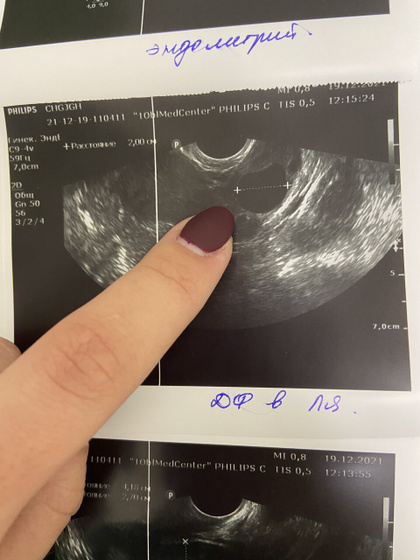

Итак, сегодня самый яркий тест на овуляцию с самого утра! Сходила сейчас на узи — ДФ 20 на 20мм, то ли лопается то ли вот вот, но ЖТ ещё не сформировано. Ещё будем стараться сегодня. Эндометрий тоже подрос до 8.8мм, врач сказала хорошей структуры